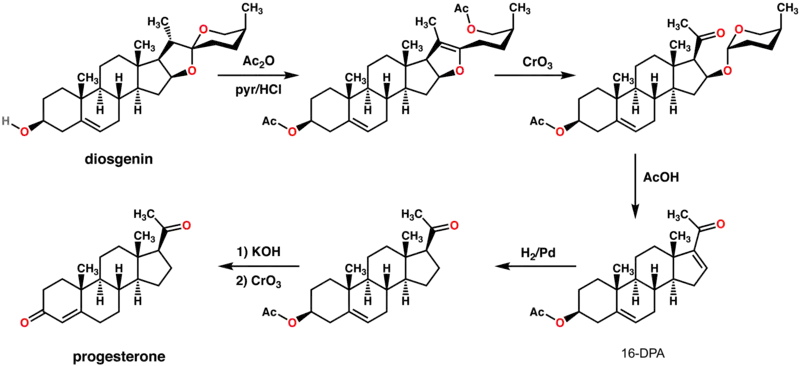

In at least one plant, Juglans regia, progesterone has been detected.[145] In addition, progesterone-like steroids are found in Dioscorea mexicana. Dioscorea mexicana is a plant that is part of the yam family native to Mexico.[146] It contains a steroid called diosgenin that is taken from the plant and is converted into progesterone.[147] Diosgenin and progesterone are also found in other Dioscorea species, as well as in other plants that are not closely related, such as fenugreek.

Another plant that contains substances readily convertible to progesterone is Dioscorea pseudojaponica native to Taiwan. Research has shown that the Taiwanese yam contains saponins — steroids that can be converted to diosgenin and thence to progesterone.[148]

Many other Dioscorea species of the yam family contain steroidal substances from which progesterone can be produced. Among the more notable of these are Dioscorea villosa and Dioscorea polygonoides. One study showed that the Dioscorea villosa contains 3.5% diosgenin.[149] Dioscorea polygonoides has been found to contain 2.64% diosgenin as shown by gas chromatography-mass spectrometry.[150] Many of the Dioscorea species that originate from the yam family grow in countries that have tropical and subtropical climates.[151]

Progesterone is commercially produced by semisynthesis. Two main routes are used: one from yam diosgenin first pioneered by Marker in 1940, and one based on soy phytosterols scaled up in the 1970s. Additional (not necessarily economical) semisyntheses of progesterone have also been reported starting from a variety of steroids. For the example, cortisone can be simultaneously deoxygenated at the C-17 and C-21 position by treatment with iodotrimethylsilane in chloroform to produce 11-keto-progesterone (ketogestin), which in turn can be reduced at position-11 to yield progesterone.[161]

Marker semisynthesis

An economical semisynthesis of progesterone from the plant steroid diosgenin isolated from yams was developed by Russell Marker in 1940 for the Parke-Davis pharmaceutical company.[162] This synthesis is known as the Marker degradation.

The 16-DPA intermediate is important to the synthesis of many other medically important steroids. A very similar approach can produce 16-DPA from solanine.[163]